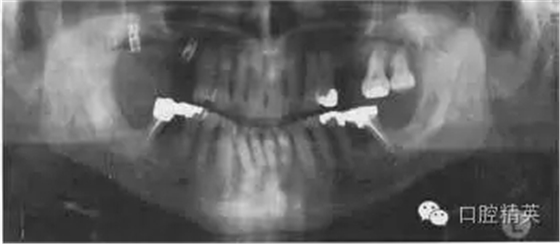

圖38.3 牙齒全口牙位曲面體層X線片顯示的治療結(jié)果

患者接受了一系列治療,療效如圖38.3。左下頜第一磨牙進(jìn)行了截根術(shù),右下頜第一磨牙進(jìn)行了半切術(shù)。這樣就消除了根分叉使患者能夠清潔。牙根周圍的炎癥得到解決。

半切術(shù)或截根術(shù)后的牙齒如果能在以后幾月甚至幾年時(shí)間中仍保持穩(wěn)定的話則最好將其修復(fù)。在這個(gè)病例中,行半切術(shù)后的磨牙牙根和前磨牙間進(jìn)行固定活動(dòng)橋修復(fù)。必須注意的是這種橋體的設(shè)計(jì)不能對(duì)牙根的牙周支持組織超負(fù)荷。這樣兩顆牙齒都保留了功能,并且非常好的暫時(shí)解決了患者的問題。